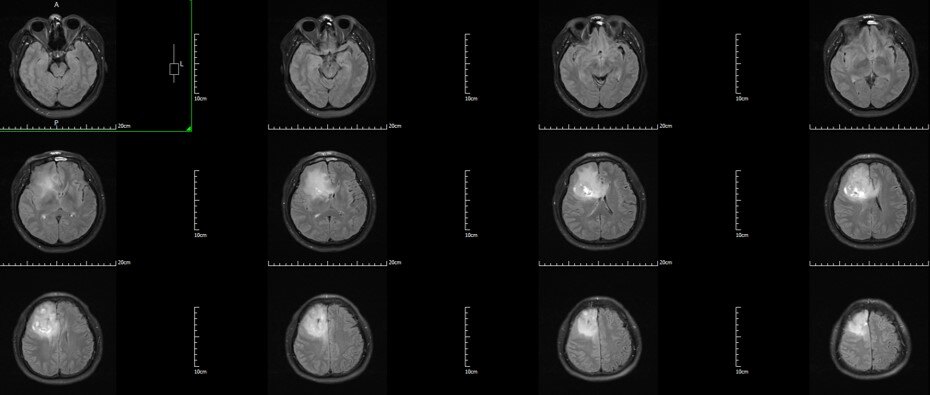

术前T2 Flair:右额-胼胝体-岛叶胶质瘤

术前T2